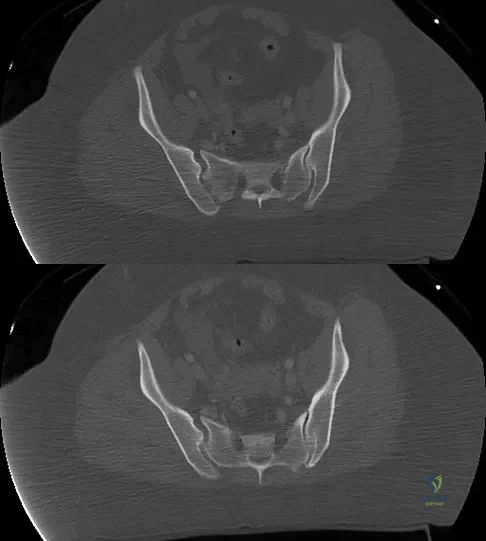

A 36-year-old woman was injured in a train derailment. She has a significant open depressed skull fracture with active bleeding, a hemopneumothorax, and blood in the left upper quadrant and colic gutter by Focused Assessment with Sonography for Trauma (FAST) examination. Additionally, she has the pelvic injury seen on the CT scans in Figures 18a and 18b. The mortality rate for this patient approaches